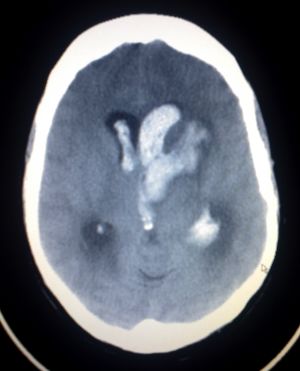

- Head CT (non-contrast)

- CT required as it is often clinically indistinguishable from SAH, ischemic stroke